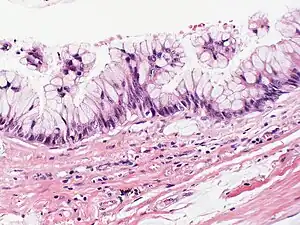

Mucinous cystadenocarcinoma

Mucinous cystadenocarcinoma is a type of tumor in the cystadenocarcinoma grouping.

It can occur in the breast[1] as well as in the ovary.[2] Tumors are normally multilocular with various smooth, thin walled cysts. Within the cysts is found a haemorrhagic or cellular debris.[2]